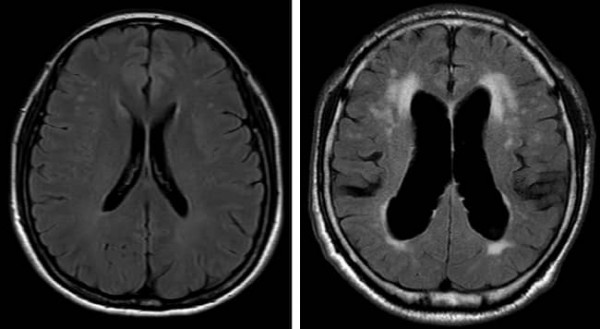

사진 1. 정상 뇌(좌)와 정상압 수두증 환자의 뇌(우) MRI 비교 영상

정상 뇌에 비해 오른쪽 정상압 수두증 환자에서는 과다 축적된 뇌척수액으로 인해 뇌실이 확장되어 있는 것을 확인할 수 있다.